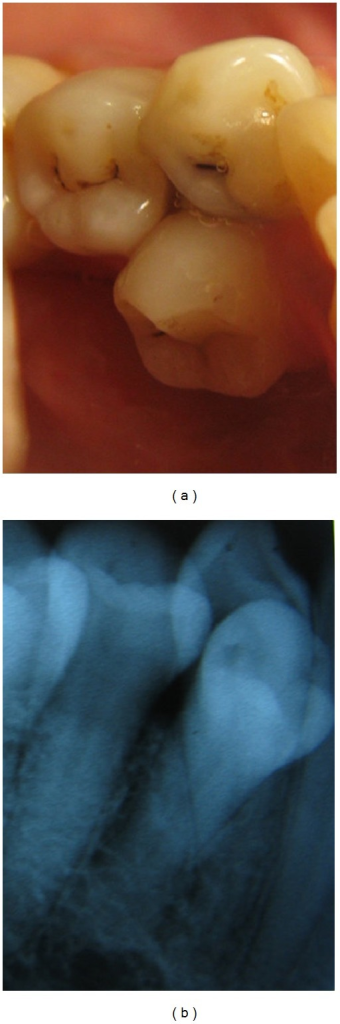

A developmental anomaly characterized by the occurrence of an extra cusp shaped as a tubercle projecting from the palatal or buccal surfaces (talon cusp) of a tooth. In the anterior dentition, dens evaginatus is more commonly found on the palatal surface of the maxillary teeth. They are easily fractured exposing the pulp.

Talon cusps may occur in isolation or alongside other dental abnormalities including peg-shaped incisors, dens invaginatus, dens evaginatus of posterior teeth, odontomata, impaction, transposition, and supernumerary or missing teeth (hypodontia).

*También denominado «diente evaginado», «tubérculo oclusal», «premolar de Leong», «premolar tuberculado» o «perla de esmalte». *Also referred to as «occlusal enamel pearl», «occlusal tubercle» or «Leong’s Premolar».